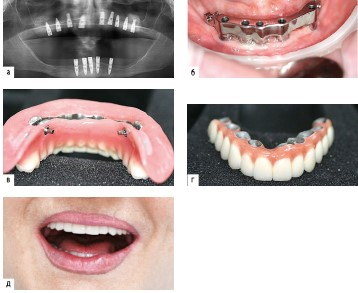

Несъемное протезирование при ПОЗ с успехом реализуется на 5-6 внутрикостных имплантатах в фронтальном отделе челюсти путем конструирования укороченного зубного ряда протеза. Исследования P. Branemark показали более высокую функциональную эффективность таких протезов по сравнению с ПСП. В ряде случаев при высокой первичной стабильности имплантатов возможно применение меньшего числа имплантатов для опоры несъемного протеза, т.е. реализация методики All-on-4, при которой установка крайних имплантатов вынужден-но производится с наклоном для профилактики травмирования n. mentalis и sinus maxillaris (рис. 2.9.11). Небольшое число опорных имплантатов, нагрузка "под углом" крайних имплантатов и реализация в этой методике немедленной нагрузки имплантатов в совокупности повышают риск функциональной перегрузки костной ткани, что обусловливает важность соблюдения показаний к такому протезированию и его планированию, а также необходимость контроля функциональной нагрузки и гигиены в период эксплуатации протеза All-on-4. Особенностями протезирования по методике All-on-4 являются: немедленная нагрузка имплантатов временным несъемным протезом с винтовой фиксацией к имплантатам; использование специальных абатментов multi-unit для компенсации наклона имплантатов; укороченный зубной ряд; протез на основе металлической балки (каркаса) с искусственными композитными или керамическими зубами.

image

Рис. 2.9.11. Концепция протезирования на имплантатах All-on-4